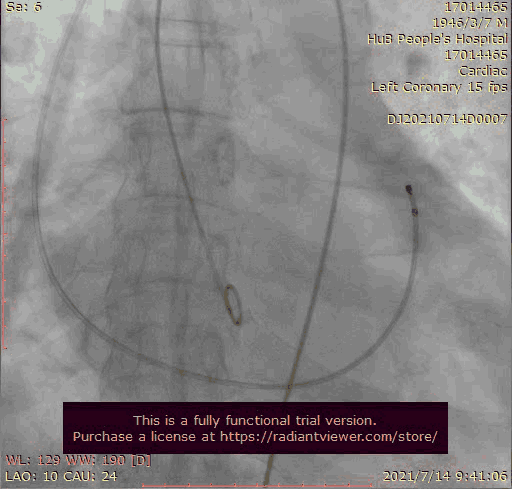

瓣膜稍高位释放

瓣膜位置稍深

使用venus-A plus回收后重新定位释放

1.在第一次释放瓣膜时,由于患者主动脉根部瓣上瓣下均比瓣环平面大,受到血流的冲击,瓣膜滑至较深的位置,使用venus-A PLUS回收